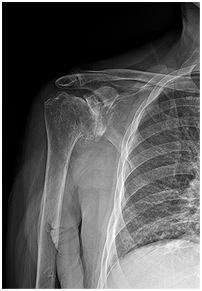

방치할 경우

발생 가능한 합병증- 유착성 관절낭염(오십견)

- 회전근개 파열로 인한 어깨관절염

- 진행된 어깨관절염